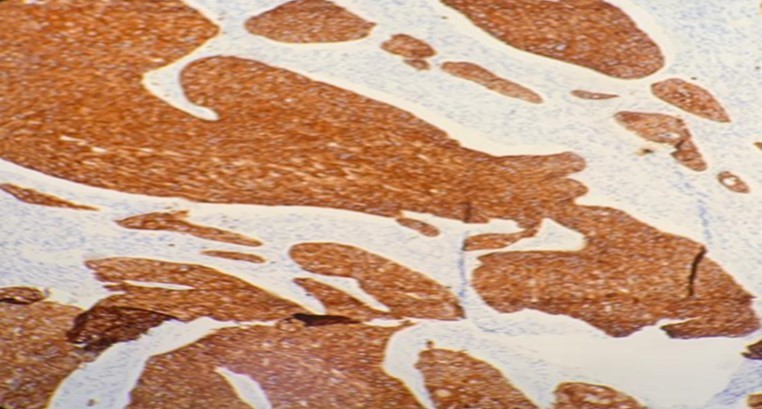

A 70-year-old gentleman, ex-smoker with no comorbid presented to us with hoarseness for 2 months in duration. He also had occasional shortness of breath. There was no constitutional symptom present. Upon our examination, the patient had soft stridor with hoarseness. There were no palpable neck nodes and laryngeal crepitus was present. On flexible nasopharyngolaryngoscopy, a fungating mass was seen occupying the whole length of the left vocal cord, with the cord in a fixed position. The right vocal cord was mobile. A high tracheostomy was done with direct laryngoscopy showing a supraglottic mass obstructing the laryngeal inlet, which is more confined to the left vocal cord and with extension into the subglottic region. Histopathology reported the mass as in favor of MEC. In microscopy, intraluminal and occasional intracytoplasmic PAS-positive diastase-resistant mucin were demonstrated. [Figure 1 & Figure 2] A contrasted-CT scan showed a huge laryngopharyngeal mass extending from the supraglottic to the infraglottic region, with no significant lymphadenopathy nor distant metastasis. The mass had no clear plane with the left thyroid and arytenoid cartilages. Subsequently, the patient underwent a total laryngectomy, left hemithyroidectomy and bilateral selective neck dissection with the histopathology reporting of high-grade MEC, with the involvement of the right level II neck node. Clinically, this is a T4aN0M0 transglottic tumor. Currently, the patient has completed adjuvant radiotherapy with monthly follow-ups at our center. He had remained well at six months follow-up.

Figure 1.Photomicrograph show presence of squamous and intermediate cells in MEC of larynx (x20 high power field)